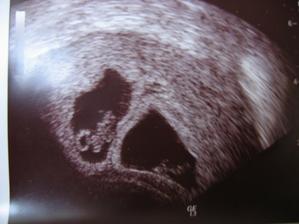

Zda sa ze nase 1. a snad aj posledne ICSI s PK sa podarilo🙂

Onedlho nás uvidíte ako malé bodky na sone,

Či budeme dve, či jedno, to je v rukách vyššej moci,